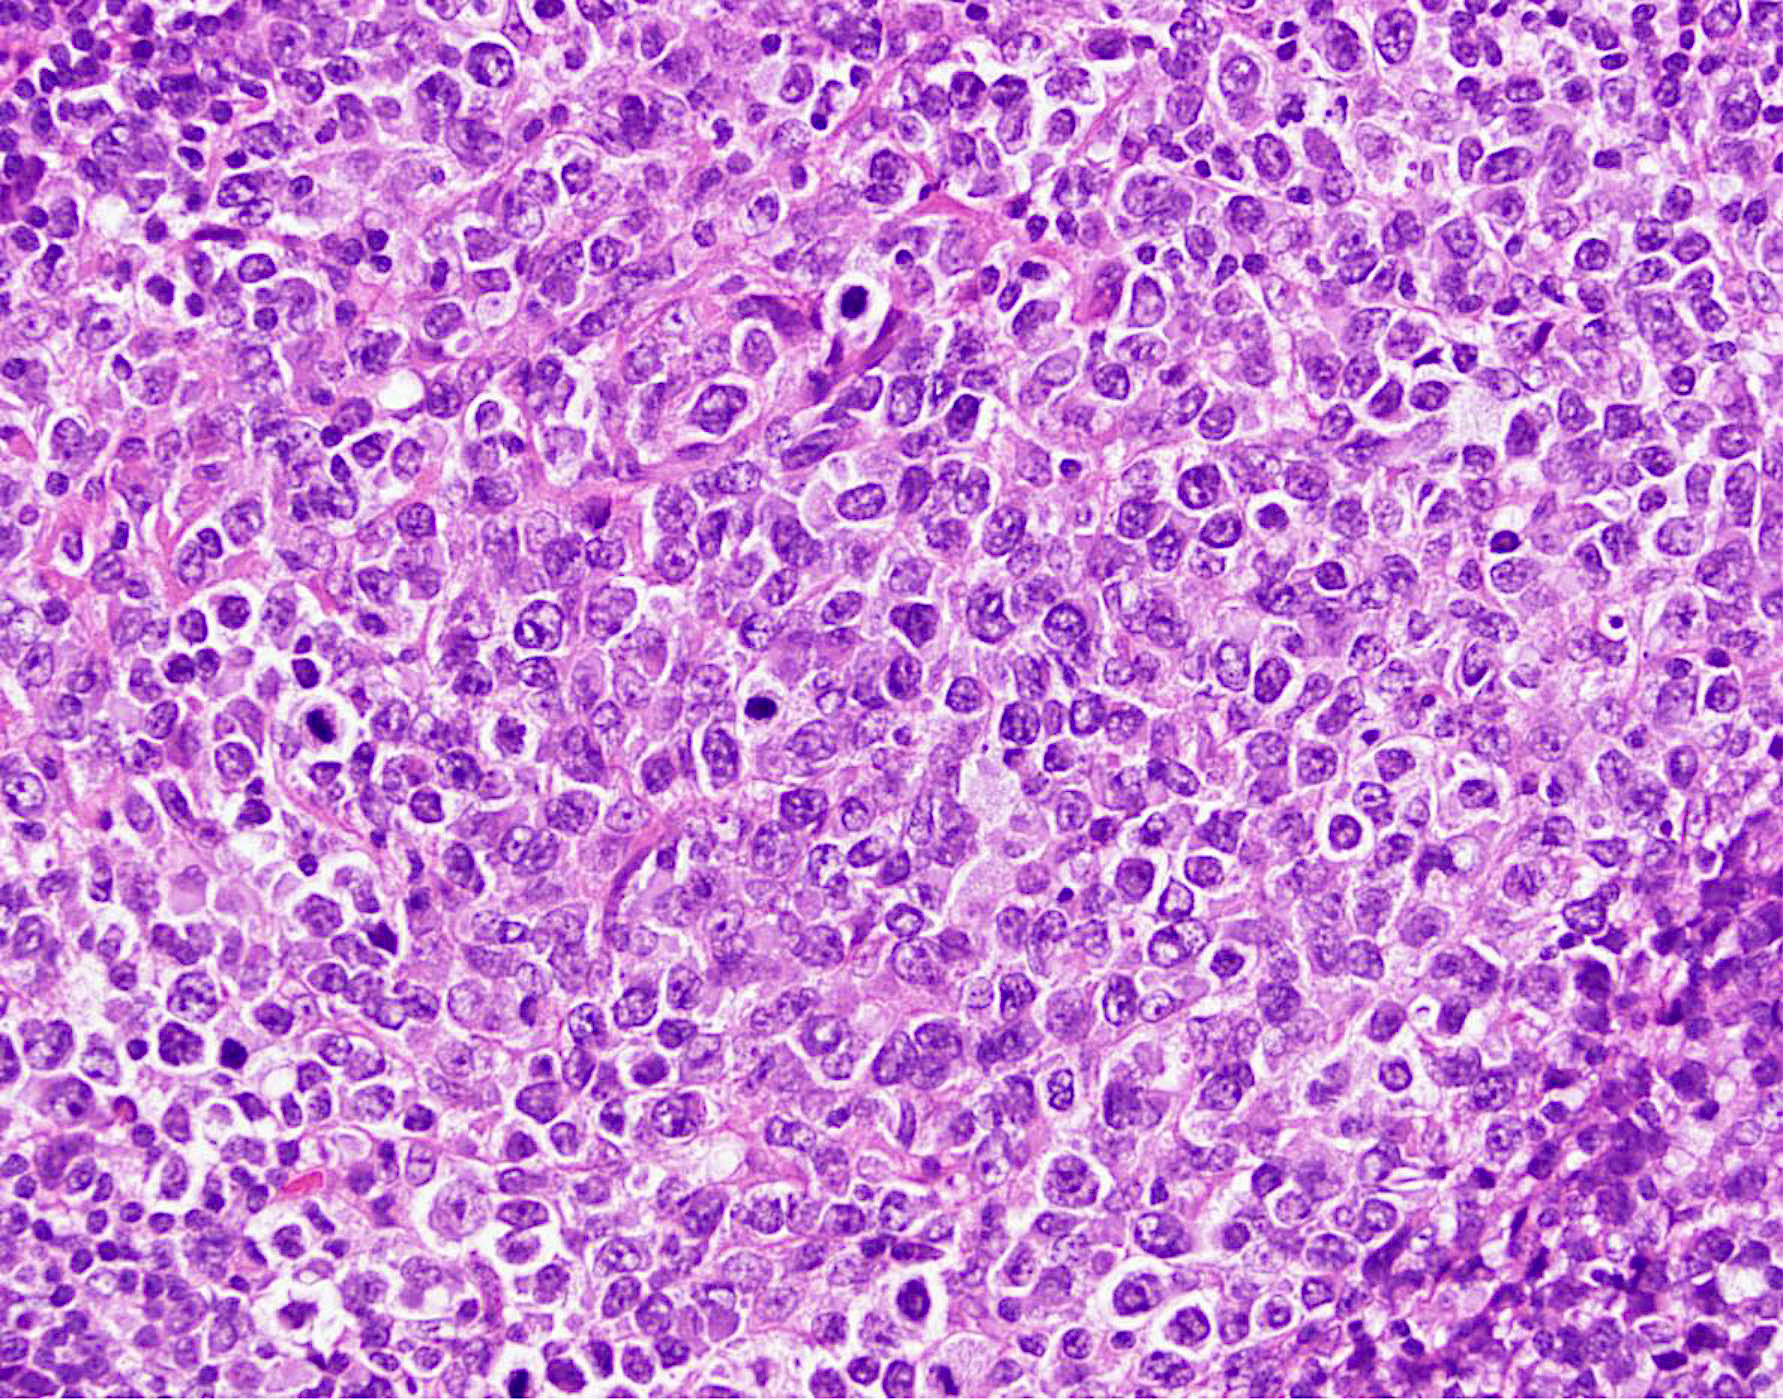

УЗИ лимфоузлов при лимфоме Ходжкина

Раздел: Образы вокруг